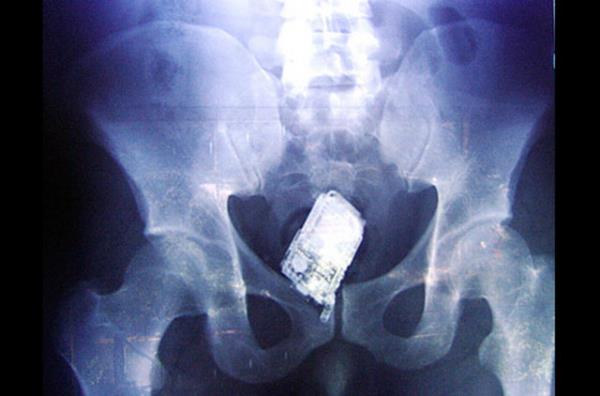

19. Bu karede ise Salvadoran Hapishanesi'nde yapılan aramada mahkumların vucutlarına gizledikleri cep telefonu gözüküyor.

Bu karede ise Salvadoran Hapishanesi'nde yapılan aramada mahkumların vucutlarına gizledikleri cep telefonu gözüküyor.